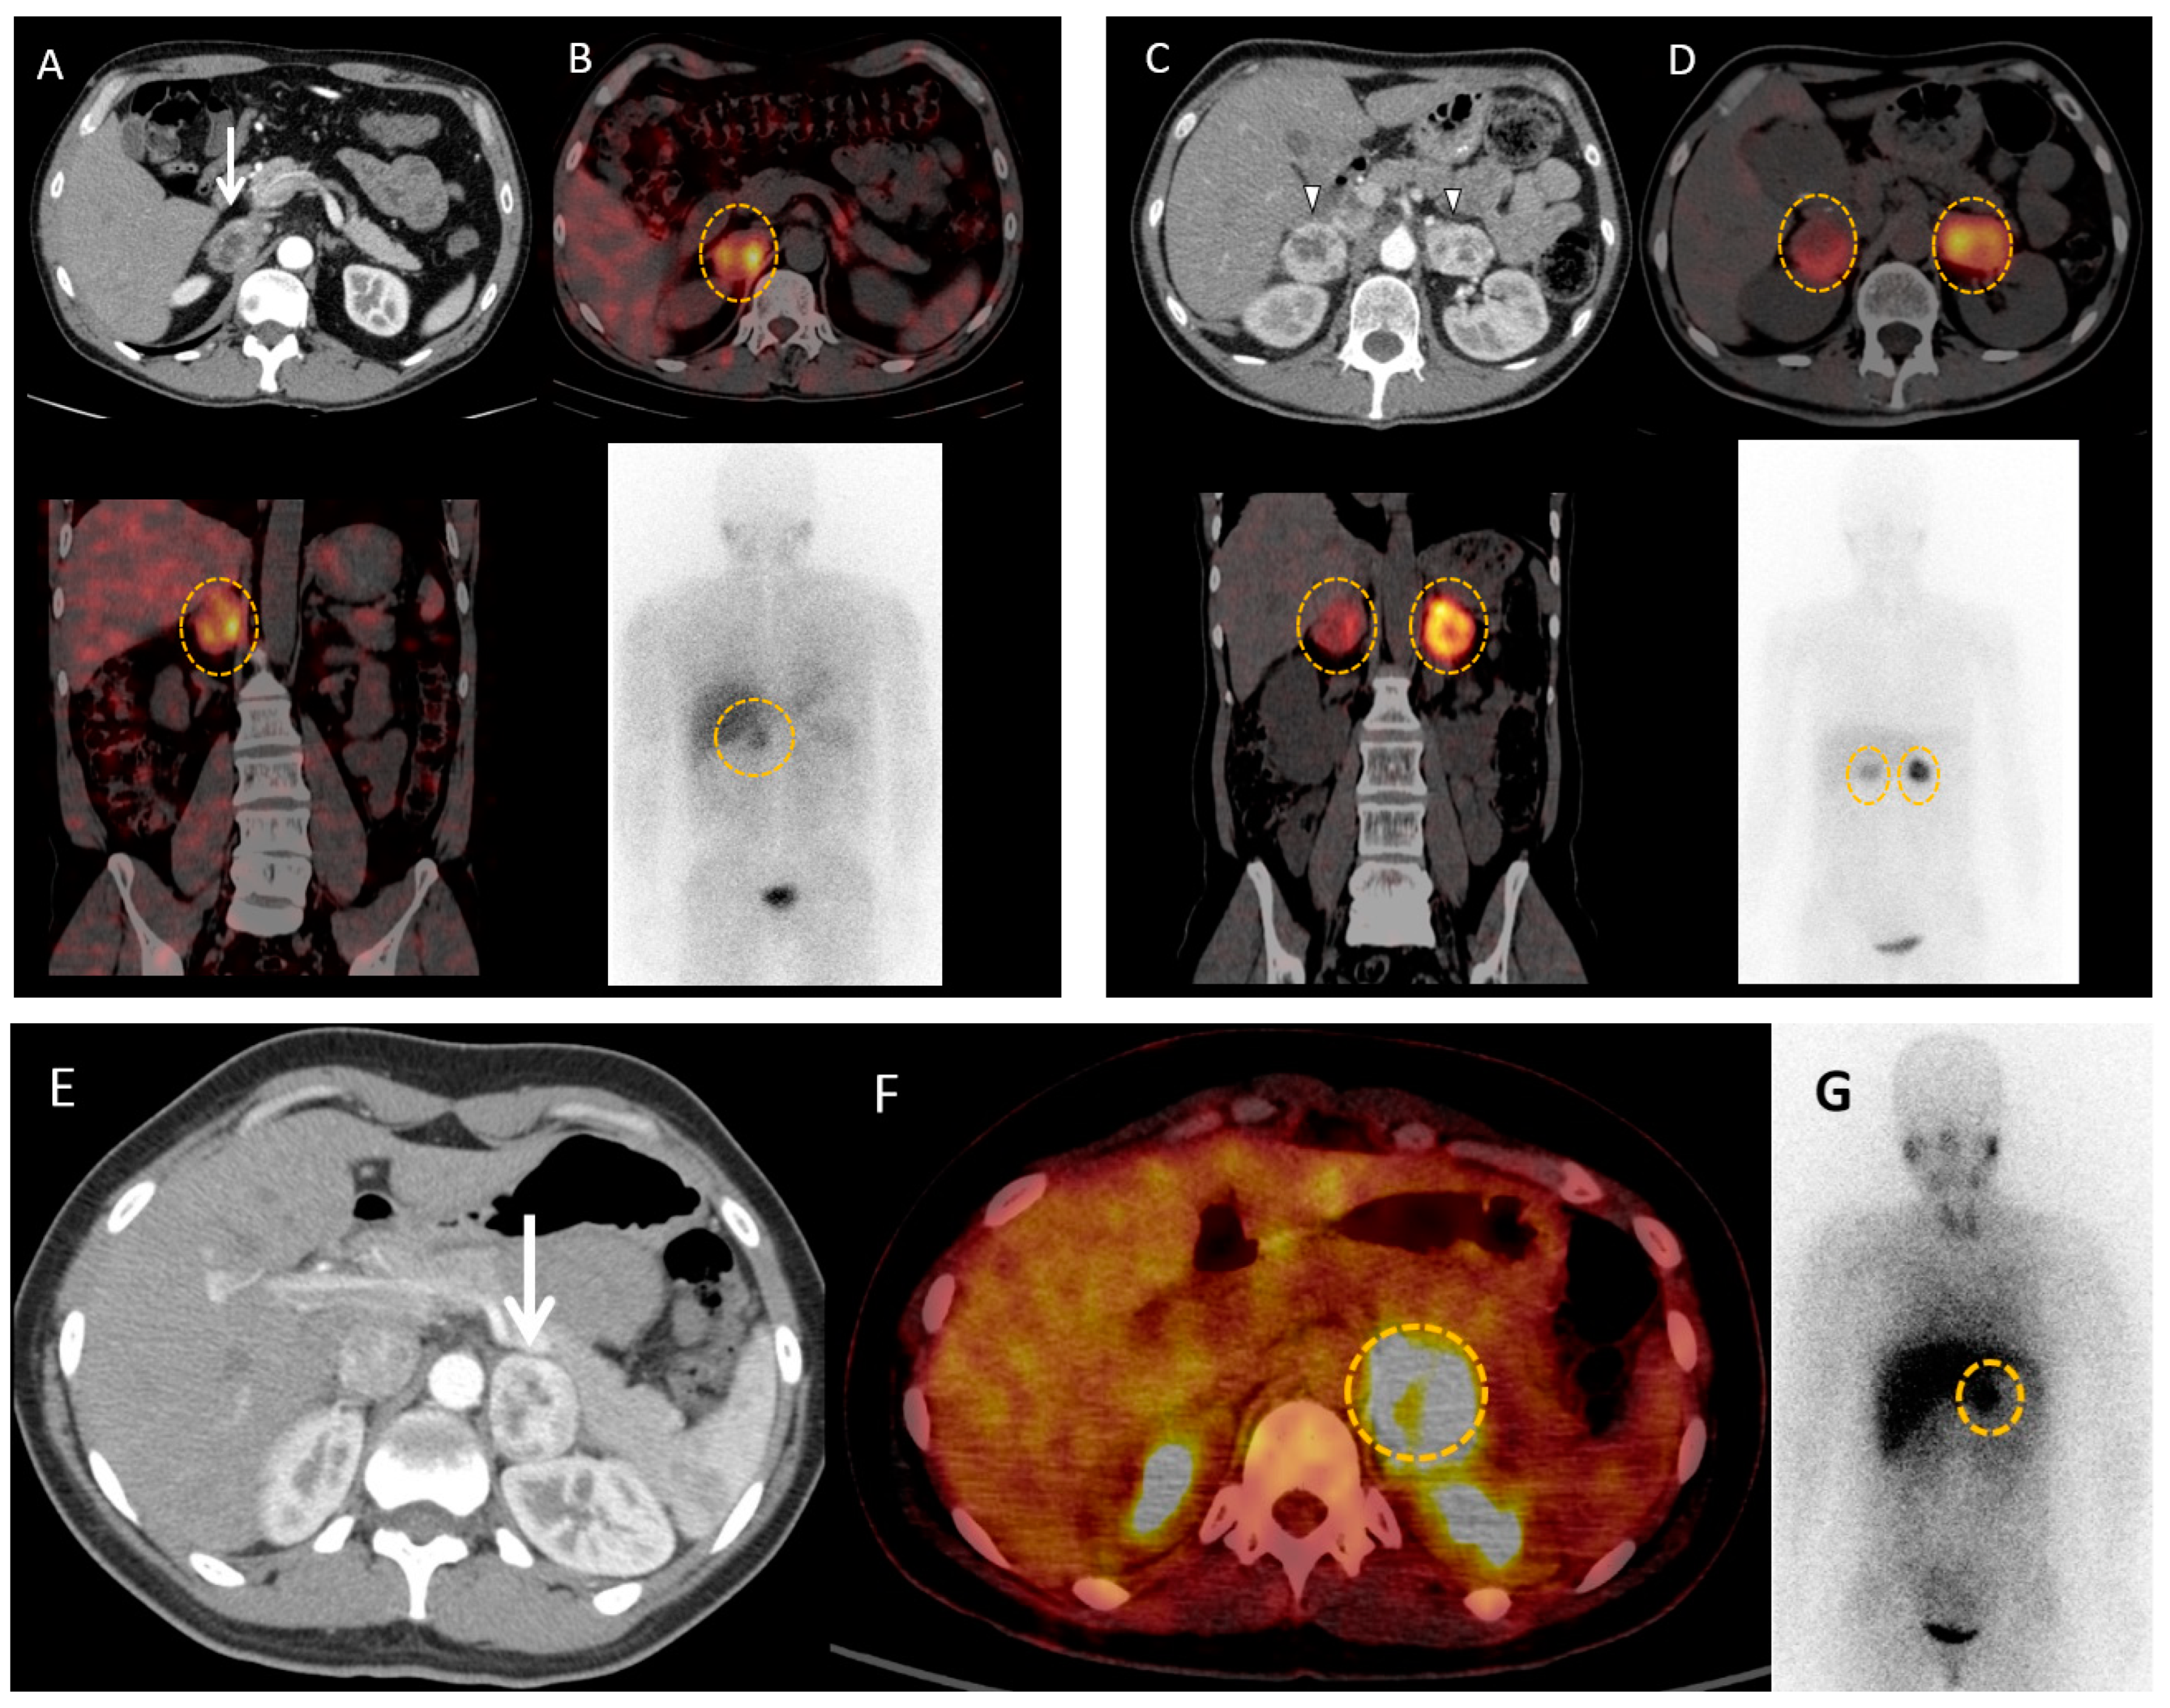

4.1. Metaiodobenzylguanidine: About the Historical Tracer

4.2. Contributions of Computed Tomography Using Dopamine and Glucose Analogues

4.3. Positron Emission Tomography with Computed Tomography Using Somatostatin Analogues

4.4. Current Guidelines for Molecular Imaging in Diagnosis and Staging of PPGLs